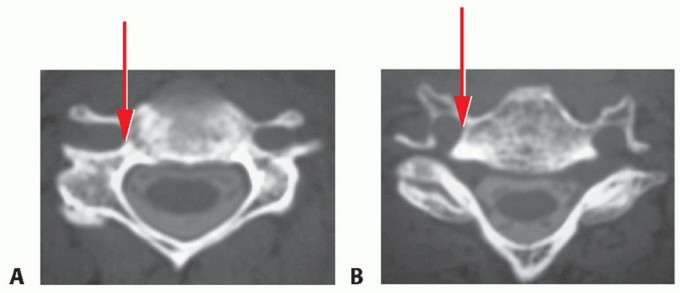

### TECH FIG 4 • A,B. Removing herniated nucleus pulposus. A. With extruded herniations, a rent in the longitudinal fibers of the PLL may be identified. A curette is then used to delineate the edges of the rent in the PLL. Once this is defined and the surgeon is certain of a plane between the PLL and underlying dura, a Kerrison is used to enlarge the edges of the rent. B. The rent has been enlarged to provide more room for finding the herniation. Curettes are then used to fish out the fragments and decompress the cord or root. C,D. Removing the PLL. C. If the PLL is intact, it can be removed by teasing in between the longitudinal fibers with a microcurette. Once a plane is established, a Kerrison can be used to remove the PLL. D. It is often easier to find this plane in the central portion of the PLL, where it is thicker, than laterally, where it is thinner and less defined. By delicately probing with a microcurette, the extruded fragment can be fished out from behind the PLL. If necessary, the defect in the PLL should be enlarged with a 2-mm Kerrison until a satisfactory portal is available to remove the herniation and ensure that all loose disc fragments have been removed. It is debatable whether the PLL needs to be resected in every case. In general, we prefer to do so, especially in cases of disc extrusion, and do not consider the decompression complete until the dural sac or exiting nerve root (depending on which is compressed based on preoperative imaging) is inspected for the absence of any further compression. If, however, the compressive lesion is an uncinate spur, with no evidence of subligamentous disc extrusion, satisfactory decompression can be achieved by removing the spurs without necessarily removing the PLL. If there is no rent in the PLL, one can be created by teasing a microcurette between the longitudinal fibers of the PLL until the curette is posterior to the PLL (TECH FIG 4C,D). Once the plane is identified between the PLL and dura, the fibers of the PLL can be resected with a curette or Kerrison rongeur. 6 Placing tension on the PLL with gentle distraction will facilitate its removal. We generally find it easier to define a plane in the PLL centrally, where it tends to be thicker, than laterally, where it is thinner and the plane with the dura is less distinct. Often, there are multiple layers of PLL, and usually in chronic cases, there is a membranous layer between the PLL and the dural sac that can be confused with dura itself. In general, if it does not look like dura, it probably is not. The portion of the PLL contralateral to the disc herniation or symptomatic foraminal stenosis does not routinely need to be removed. ### Avoiding Vertebral Artery and Neural Injury Before surgery, the surgeon should always scrutinize the position of the vertebral arteries on the preoperative scans to rule out the presence of aberrancies in their course (TECH FIG 5). Aberrations typically occur within the vertebral body. However, it is not uncommon for one vertebral artery to be closer to the uncinate on one side versus the other, which would mandate greater caution when approaching that side.3 In the absence of vertebral artery aberrancy, laceration to the vertebral artery is most likely to occur from the surgeon's loss of orientation to the uncinates. The uncinates define the safe zone for the vertebral artery and the effective zone for the decompression. It is imperative to define and maintain orientation with both uncinates at all times during anterior cervical surgery.

TECH FIG 5 • A,B. Vertebral artery anomalies. A. The right transverse foramen (arrow) courses somewhat more medially than the one on the left. This is a subtle but potentially important anomaly to observe preoperatively. B. The anomaly occurs within the vertebral body rather than at the disc space level where the right transverse foramen is now more normally positioned (arrow). C. Penfield lateral to the uncinate. In certain cases, especially if there is a deformity, the location of the lateral border of the uncinate (ie, the safe zone for the vertebral artery) may not be obvious after elevation of the longus colli. Placing a Penfield dissector no. 4 gently underneath the longus colli, retracting it laterally, and then hooking the dissector lateral to the uncinate will allow for safe orientation to the vertebral artery. The vertebral artery is typically in the anterior two-thirds of the disc space. When curetting disc material in this area, a vertebral artery laceration might occur if the curette strays lateral to the lateral border of the uncinate. If in doubt, a Penfield dissector can be used to identify the lateral border of the uncinate processes to avoid straying laterally and injuring the vertebral arteries, which are generally a few millimeters from the lateral edge of the uncinate (TECH FIG 5C). ### Graft Sizing and Placement Ultimate graft height can be estimated preoperatively from the preoperative lateral film. In many cases, a graft height of 2 to 3 mm more than that measured on the preoperative lateral film will be the optimal choice. Ideally, the anteroposterior depth of the graft should be a few millimeters less than that of the disc space, such that the graft can be countersunk 2 mm without entering the spinal canal. The final height of the graft can be determined after endplate preparation with sizers that accompany commercial grafts (TECH FIG 6). The trials should be lightly malleted into position under gentle Caspar pin distraction. A snug fit in the distracted position will ensure an excellent fit after removal of distraction pins. If the trial does not fit but the next smaller trial seems too loose, the surgeon should identify the area of impingement and lightly decorticate that area. Then, the trial is reinserted. For multilevel ACDF, we prefer to decompress and graft each segment before proceeding to the next level. One way to enhance fusion rates is to place as much bone into the interspace as possible. A wide decompression also provides greater room for bone graft. Space lateral to the structural bone graft in the uncinate regions can be packed with bone or bone graft substitutes. 7 If the space is wide enough, two grafts can be placed side by side to fill the entire space.